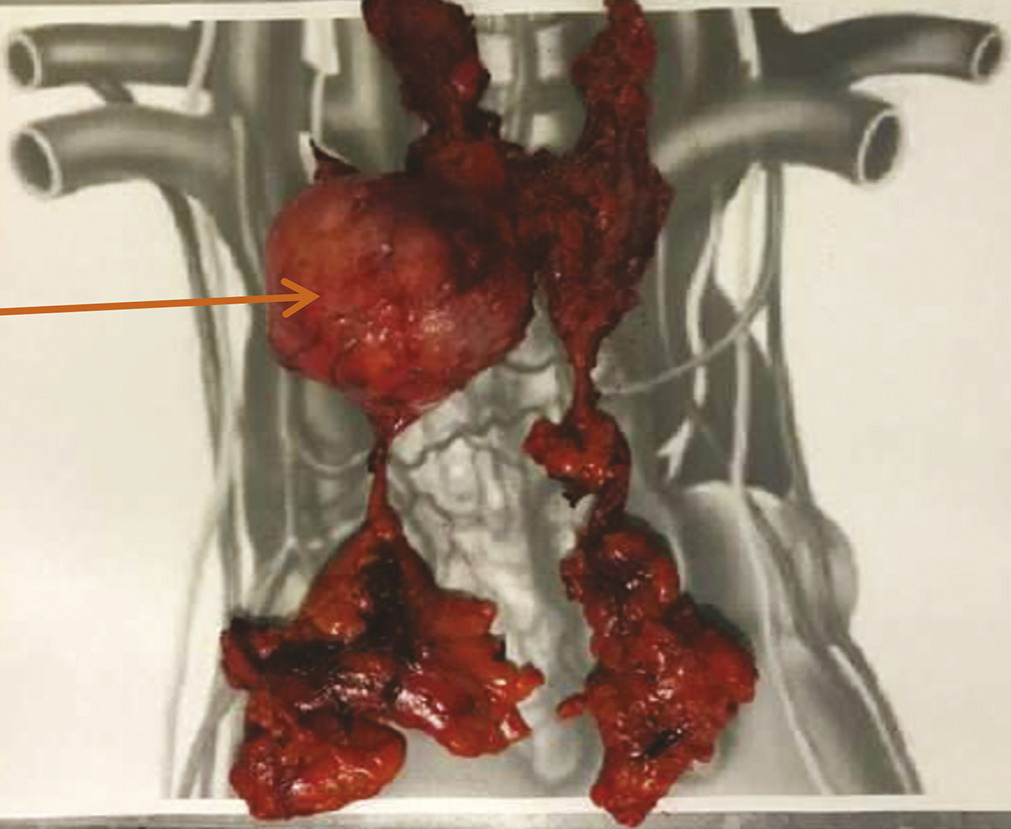

Une évaluation neurologique est nécessaire afin d’encadrer le geste chirurgical. Mme C. reçoit ainsi en préopératoire une injection d’immunoglobulines par voie intraveineuse afin d’éviter une exacerbation des symptômes myasthéniques en périopératoire. La chirurgie consiste en une sternotomie médiane, avec exérèse de la tumeur médiastinale et bilobectomie supérieure. Face à l’envahissement péricardique et pulmonaire adjacent, la tumeur est classée stade III (dans la classification de Masaoka-Koga), et stade T3N0M0, soit IIIA (dans la classification TNM). Les marges de résection sont saines (R0).6, 7